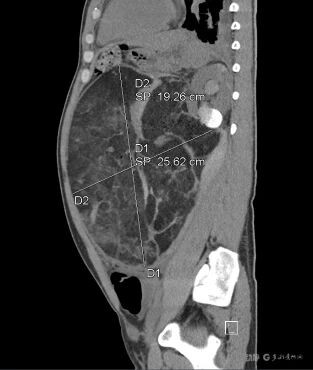

据了解,长期疏于体检的张先生(化名)因突发剧烈腹痛、头晕心慌急诊入院。当时他已出现血压下降、心率加快等休克前兆。急诊CT显示:左肾巨大错构瘤破裂出血,肿瘤体积达27cm×25cm,严重压迫周围脏器,活动性出血持续不止。

近日,因长期疏于体检,张先生突发剧烈腹痛并伴头晕心慌,被紧急送至贵州医科大学附属医院。急诊CT检查结果令人震惊:其左肾内长有一个体积达27cm×25cm的巨大错构瘤,并且已经破裂出血。

急诊CT显示,患者左肾巨大错构瘤已破裂出血。

33 岁的张先生(化名)突发剧烈腹痛伴头晕心慌,来到贵医附院看诊。医生了解到,张先生长期疏于体检,医院急诊CT 检查确诊为左肾巨大错构瘤破裂出血—— 肿瘤体积竟达 27cm×25cm,相当于一个篮球大小!